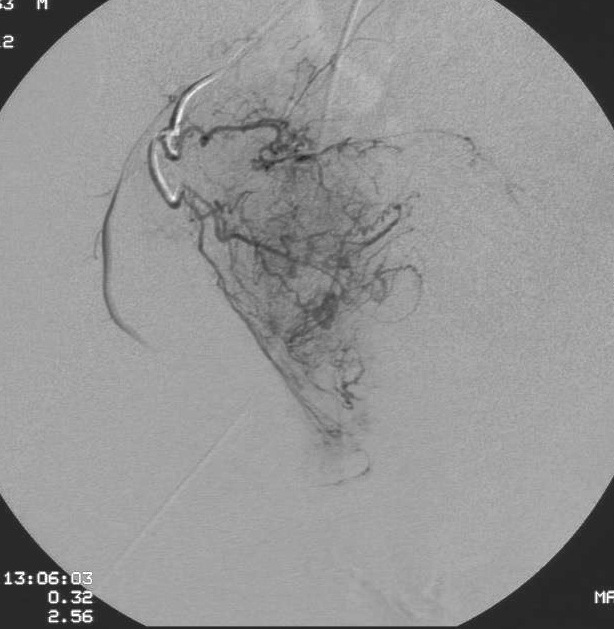

4. 5F RUC 或 COBRA 2 + 微导管进入髂内动脉前分支及前列腺动脉并造影证实。

5F RUC导管(子宫动脉导管)

5. 髂内动脉造影显示髂动脉向前的分支(同侧斜位35°,头侧斜(caudal-craneal10°)。进行选择性前列腺动脉导管术;或称为PROVISO

P= Pudendal;R=Rectal;O=Obturator;V=? I=inferior;O=Oblique。同时充盈Foley尿管便于识别。

微导管的末端位置(the microcatheter is advanced distally in the prostatic artery before embolization)